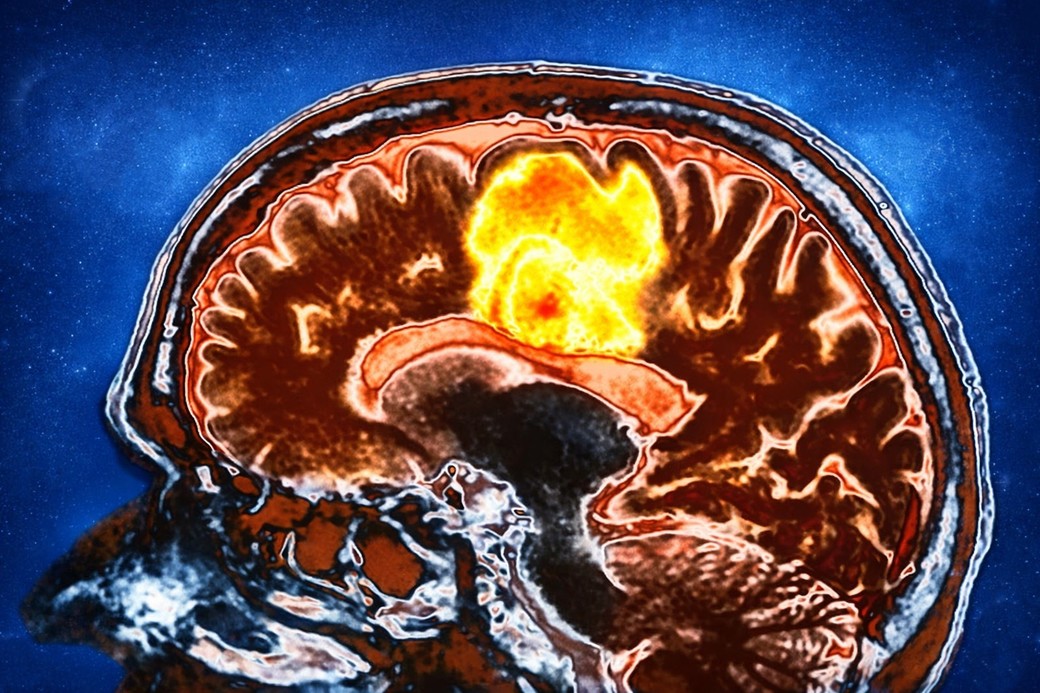

Glioblastomul este una dintre cele mai agresive forme de cancer cerebral, cu opţiuni terapeutice limitate şi un prognostic rezervat. Un studiu clinic de mici dimensiuni indică faptul că o combinaţie de două suplimente frecvent utilizate ar putea influenţa anumiţi markeri biologici asociaţi cu această boală, deschizând o potenţială direcţie de cercetare care urmează să fie evaluată în studii mai ample.

Un grup de cercetători de la Tata Memorial Hospital din India a evaluat efectele unei combinaţii de resveratrol şi cupru asupra ţesutului tumoral la pacienţi cu glioblastom, într-un studiu preliminar desfăşurat înainte de intervenţia chirurgicală. Rezultatele iniţiale asociază combinaţia de suplimente cu modificări biologice favorabile în glioblastom.